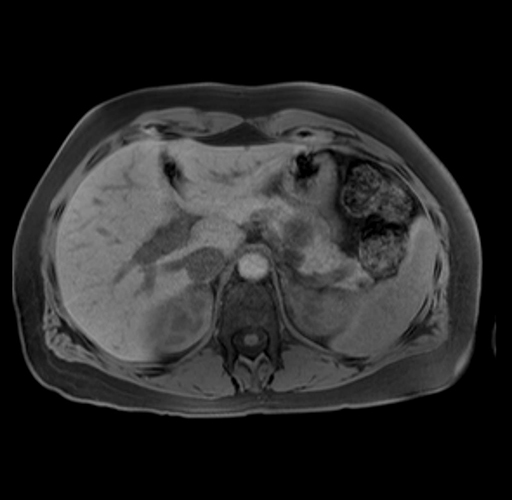

Imaging Analysis

Look through the patient's CT scan to identify any areas of concern for the necessary procedure.

Based on your CT findings, which issue(s) are present and would give reason for "planned slowing down moment(s)" in this case?

Considering a standard distal pancreatectomy procedure, what step(s) of the operation would you do differently in this case?